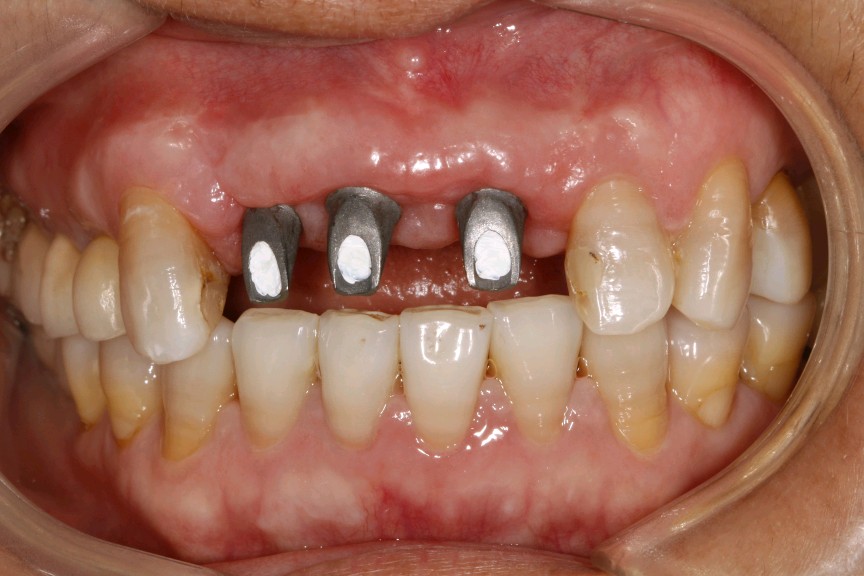

患者女,四十岁,前牙松动一个月。口内检查:12,11,21连冠修复,松动(+++),12冠根折。X线显示:骨密度良好,牙槽骨骨量不足。治疗计划:拔除+植人骨粉骨膜+种植修复。

术前